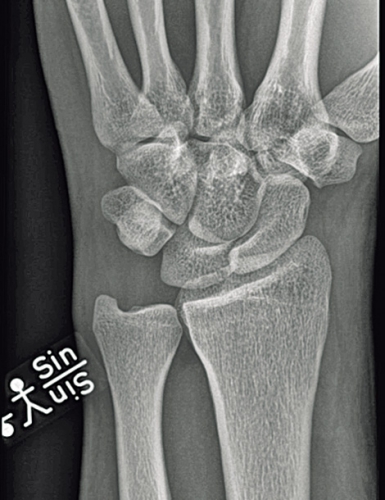

Observera att samtidiga ipsilaterala skador, t ex armbågsluxation, är vanliga. Akut karpaltunnelsyndrom förekommer i ungefär en tredjedel av fallen. Diagnosen ställs på röntgenbilden: Leta efter oordning bland karpalbenen och brutna Gilulas linjer! Observera att luxationen främst framträder på sidobilden, medan frontalbilden kan förefalla närmast normal. Man ska vara frikostig med datortomografi (DT), som kan påvisa mer ovanliga skademönster och synliggöra associerade karpala frakturer. Scaphoideum- och capitatum-frakturer är i detta sammanhang vanligast förekommande. DT kan också underlätta valet av snittföring. Observera att dessa skador alltid kräver öppen kirurgi, även om primär reposition lyckas och kontrollröntgen inte visar några frakturer. Enbart perkutan stiftfixation är aldrig till fyllest.

Skafolunära ligamentskador. När det gäller skafolunära ligamentskador är ligamentet mellan scaphoideum, trapezium och trapezoideum (STT), volara ligamentet mellan scaphoideum och capitatum (SC) och volara ligamentet mellan radius, scaphoideum och capitatum (RSC) viktiga s k sekundära stabilisatorer. När dessa ligament gradvis tänjs ut resulterar det i en karpal kollaps med statisk instabilitet som följd. På en röntgenbild i obelastat läge framträder då en volar flexionsfelställning av scaphoideum och en dorsal rotation av lunatum (DISI). Vanligtvis finner man då på röntgenbilden också ett »ring sign« i scaphoideum till följd av scaphoideums rotation.

För diagnos krävs provokationsröntgen. Det innebär att röntgenbilderna tas i vissa lägen, t ex ulnardeviation, eller under belastning, t ex med knuten hand. Allvarligare partiella ligamentskador och totala ligamentrupturer kan, om de inte fås att läka adekvat, leda till progredierande karpal dysfunktion på grund av överbelastning av kvarvarande ligament och angränsande ledytor.